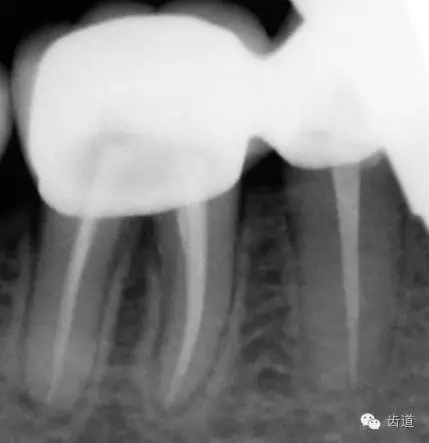

2、45,46術(shù)前片顯示根管上段充填物,根管影像不清晰,少許根尖暗影

45,46去除原充填物和齲壞,揭全髓室頂,46探及近頰近舌遠(yuǎn)中三根管,45單根管,超聲輔助清理髓腔及根管,去除根管內(nèi)充填物,根管下段細(xì)小堵塞欠通暢,8號/10號C銼疏通根管,pathfile+protaper鎳鈦根管預(yù)備,熱牙膠根管充填。